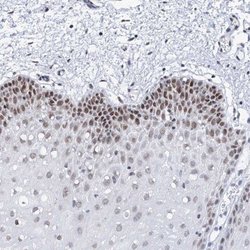

Immunohistochemistry

ABIN4355559 IHC

Other validation